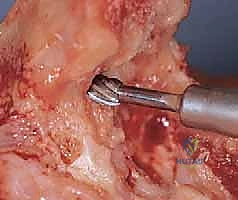

يتم تجميع المفصل الصناعي وربط الجزء العضدي بالجزء الزندي بواسطة مسمار مفصلي (Pin)، مما يعيد للمرفق استقراره المفقود.

6. الاختبار الحركي والإغلاق

قبل إغلاق الجرح، يقوم الدكتور هطيف باختبار النطاق الحركي للمرفق الجديد (الثني، البسط، الدوران) للتأكد من سلاسة الحركة وعدم وجود أي احتكاك أو انحشار.

بعد التأكد من الأداء المثالي، يتم نقل العصب الزندي إلى مكان آمن (Ulnar Nerve Transposition) لمنع تهيجه مستقبلاً، ثم تُغلق العضلات والأنسجة والجلد بخيوط تجميلية دقيقة لتقليل الندبات. يتم وضع أنبوب تصريف صغير (درنقة) وضمادة معقمة.